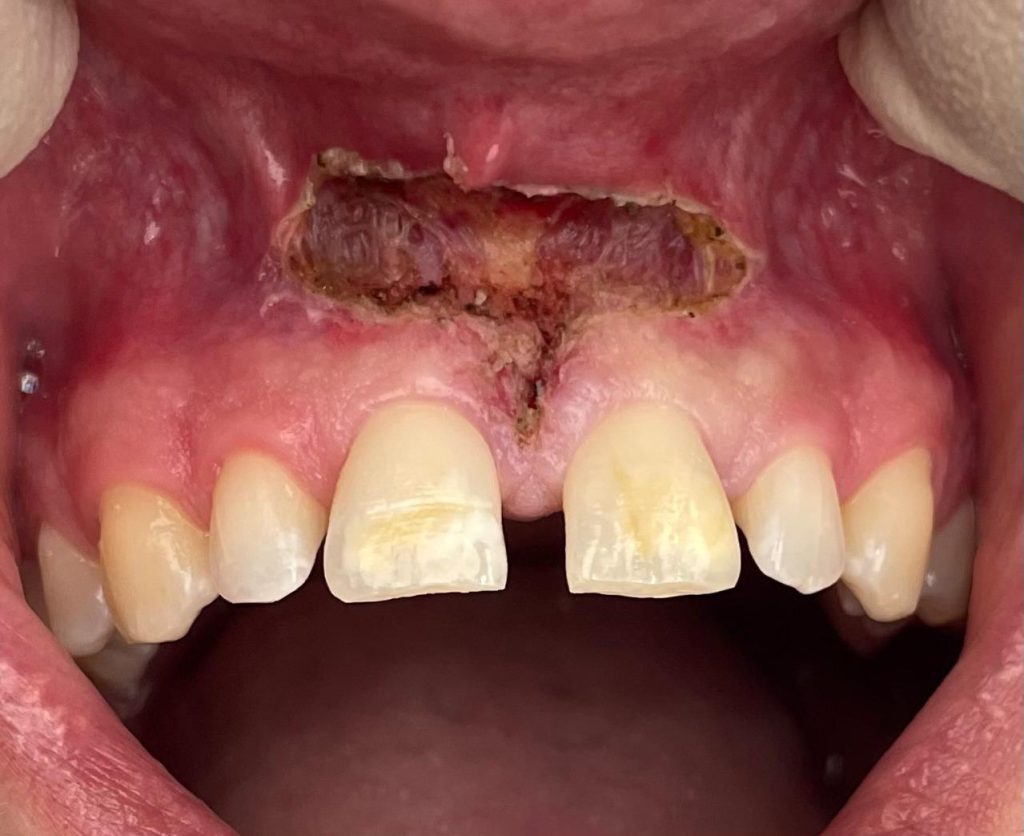

Questa settimana vi presentiamo il caso di frenulectomia del labbro superiore e inferiore eseguita con un laser KTP.

Nelle immagini, oltre alle fasi dell’intervento, è possibile osservare la guarigione dei tessuti dopo 10 giorni.